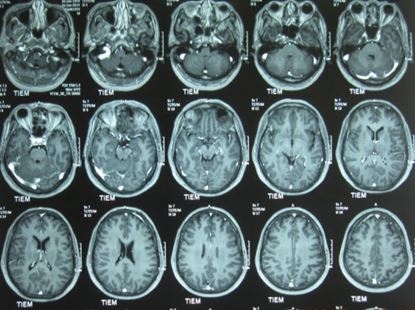

1. Chụp cộng hưởng từ sọ não: không thấy hình ảnh bất thường (hình 4)

Hình 4: Hình ảnh chụp cộng hưởng từ sọ não bình thường